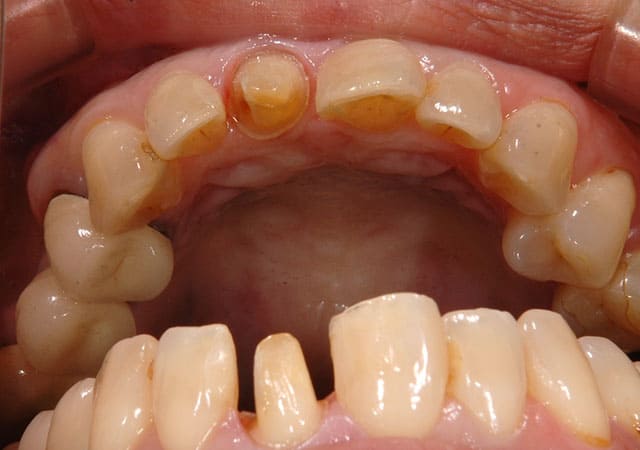

左上の前歯の見た目が気になることを主訴に来院されました。

虫歯を除去後、神経が露出しないように丁寧に削合しました。

仮歯に置き換え、見た目の確認をしてもらいました。

反対側に近い形となっており、元々の歯よりも大きいため、全体的に小さくしてほしいとの希望でした。

患者さんの希望を反映した補綴物が完成しました。

患者さんの希望の色味、形となりとても満足いただけました。